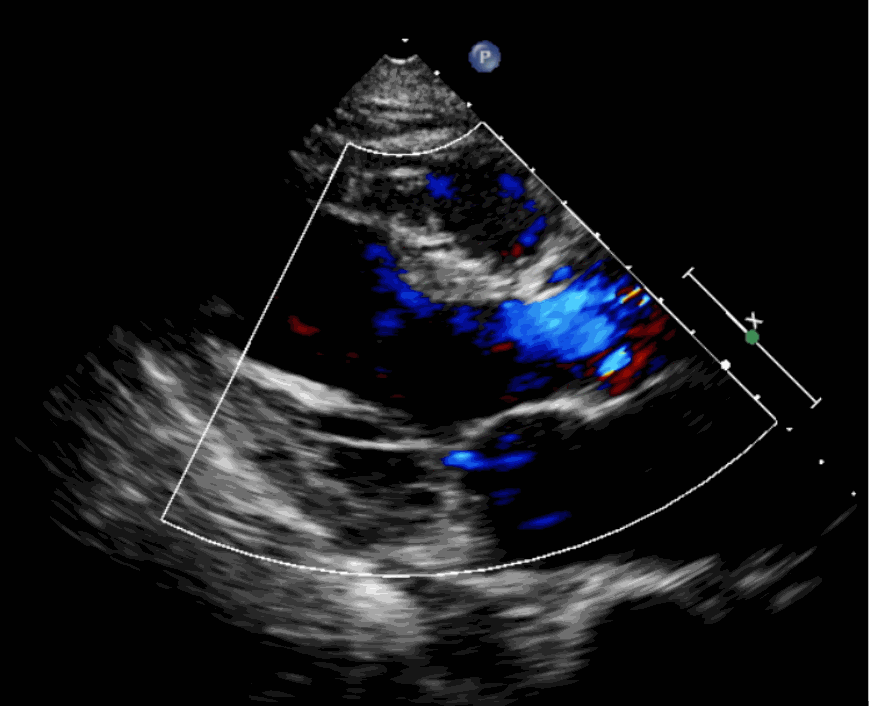

該例患者為62歲,女性,因“間歇性心悸、胸悶、氣短、胸痛1年,加重1周”之主訴入院。入院診斷:主動(dòng)脈瓣重度關(guān)閉不全,二尖瓣、三尖瓣輕度關(guān)閉不全,心功能III級(jí);冠狀動(dòng)脈粥樣硬化性心臟病。行心臟超聲心動(dòng)圖提示“主動(dòng)脈瓣重度關(guān)閉不全;瓣口水平以下左室下壁、后下壁搏幅減低;EF值 0.30,左房、左室大、右房大小正常高限;二尖瓣、三尖瓣關(guān)閉不全;輕度肺動(dòng)脈高壓(收縮壓42mmHg);主動(dòng)脈硬化;左室收縮功能重度減低。經(jīng)心血管外科劉洋、楊劍教授、麻醉科陳敏教授及超聲科孟欣教授等專家團(tuán)隊(duì)綜合評(píng)估,判定患者為外科手術(shù)高危患者。

手術(shù)采用經(jīng)心尖入路,對(duì)患者進(jìn)行全麻后,在左側(cè)心尖處做3-4cm微創(chuàng)手術(shù)切口,在DSA及超聲引導(dǎo)下手術(shù)順利完成。從導(dǎo)入器械到完成瓣膜置入,僅耗時(shí)約10分鐘。術(shù)后即刻主動(dòng)脈瓣返流程度由術(shù)前大量返流轉(zhuǎn)為消失,患者于導(dǎo)管室拔除氣管插管,次日由ICU轉(zhuǎn)入普通病房。

術(shù)前超聲影像圖